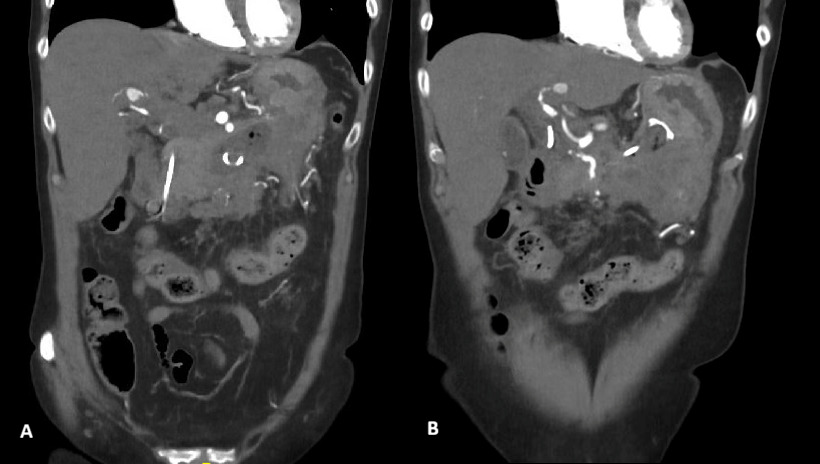

On this interval CT imaging, the distal common hepatic artery (CHA) and the proximal left (LHA) and right hepatic arteries (RHA) were noted to be non-opacified, with soft tissue attenuation tracking along the expected course of these vessels. In the clinical context, these findings were most consistent with arterial thrombosis with associated vessel expansion or pseudoaneurysm formation, giving rise to the observed imaging appearance.

Further evaluation with Doppler ultrasound demonstrated non-occlusive bland thrombus within the common hepatic and left hepatic arteries. A subsequent CT angiogram (CTA), performed four weeks after the initial CT, confirmed the presence of multiple visceral pseudoaneurysms involving the hepatic arterial system. These included aneurysms of the right hepatic artery measuring 5.5 mm and 5.8 mm, intermediate hepatic artery aneurysms measuring 7.7 mm, 5.7 mm, and 14 mm, and a left hepatic artery aneurysm measuring 10.4 mm. Additionally, the coeliac trunk appeared diffusely aneurysmal with associated luminal irregularity (figure 3). All aneurysms demonstrated interval enlargement compared with prior imaging (Figure 2). Notably, during this period, the patient’s inflammatory markers and liver function tests had normalised.